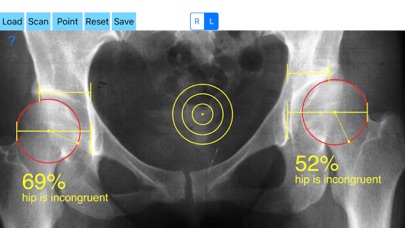

Treatment of incongruity is paramount importance because you have to address it early and the treatment of choice are usually corrective hip osteotomies. In order-from one hand to avert the natural course to the progression of secondary osteoarthritis (OA) and from another hand to avoid- in developing skeleton - to deteriorate more the hip dysplasia the congruity must be objectively and thoroughly evaluated especially at follow up of these procedures in both congruent and incongruent hips. Congruity between the femoral head and acetabulum is determined by the percentage of femoral head covered by the bony acetabulum. The congruity index (CI) is calculated (A/B- ratio converted to a percentage) by diving the (A) distance by the distance (B), where distance (A) is the distance between the teardrop to the lateral acetabular margin and (B) is the distance from the teardrop again to the lateral femoral head edge.

-Offers a very convenient way to determine the most accurate possibly way an objective value of congruity. By clicking three point at the x-ray picture on your iPhone screen and inserting the side the App calculates the congruity index (CI) which is the percentage of femoral head covered by the bony acetabulum. Congruity between the femoral head and acetabulum is expressed in percentage. Values of Coverage less than 75% is considered pathologic in another words the hip is incongruent